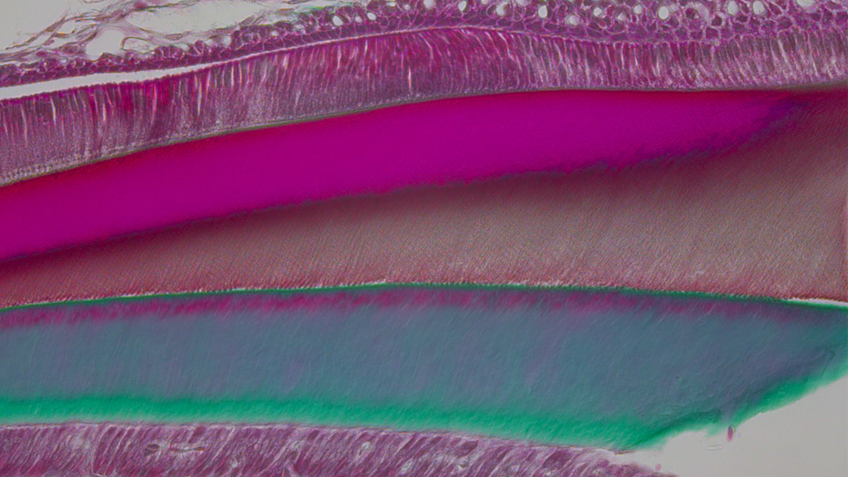

Même à faibles doses, l’exposition au DEHP altère le développement des dents

Certains perturbateurs endocriniens ont déjà été associés à une altération de la qualité de l’émail des dents. Après avoir montré les effets délétères du bisphénol A sur le développement des dents, une équipe de recherche (Université Paris Cité -Inserm –...